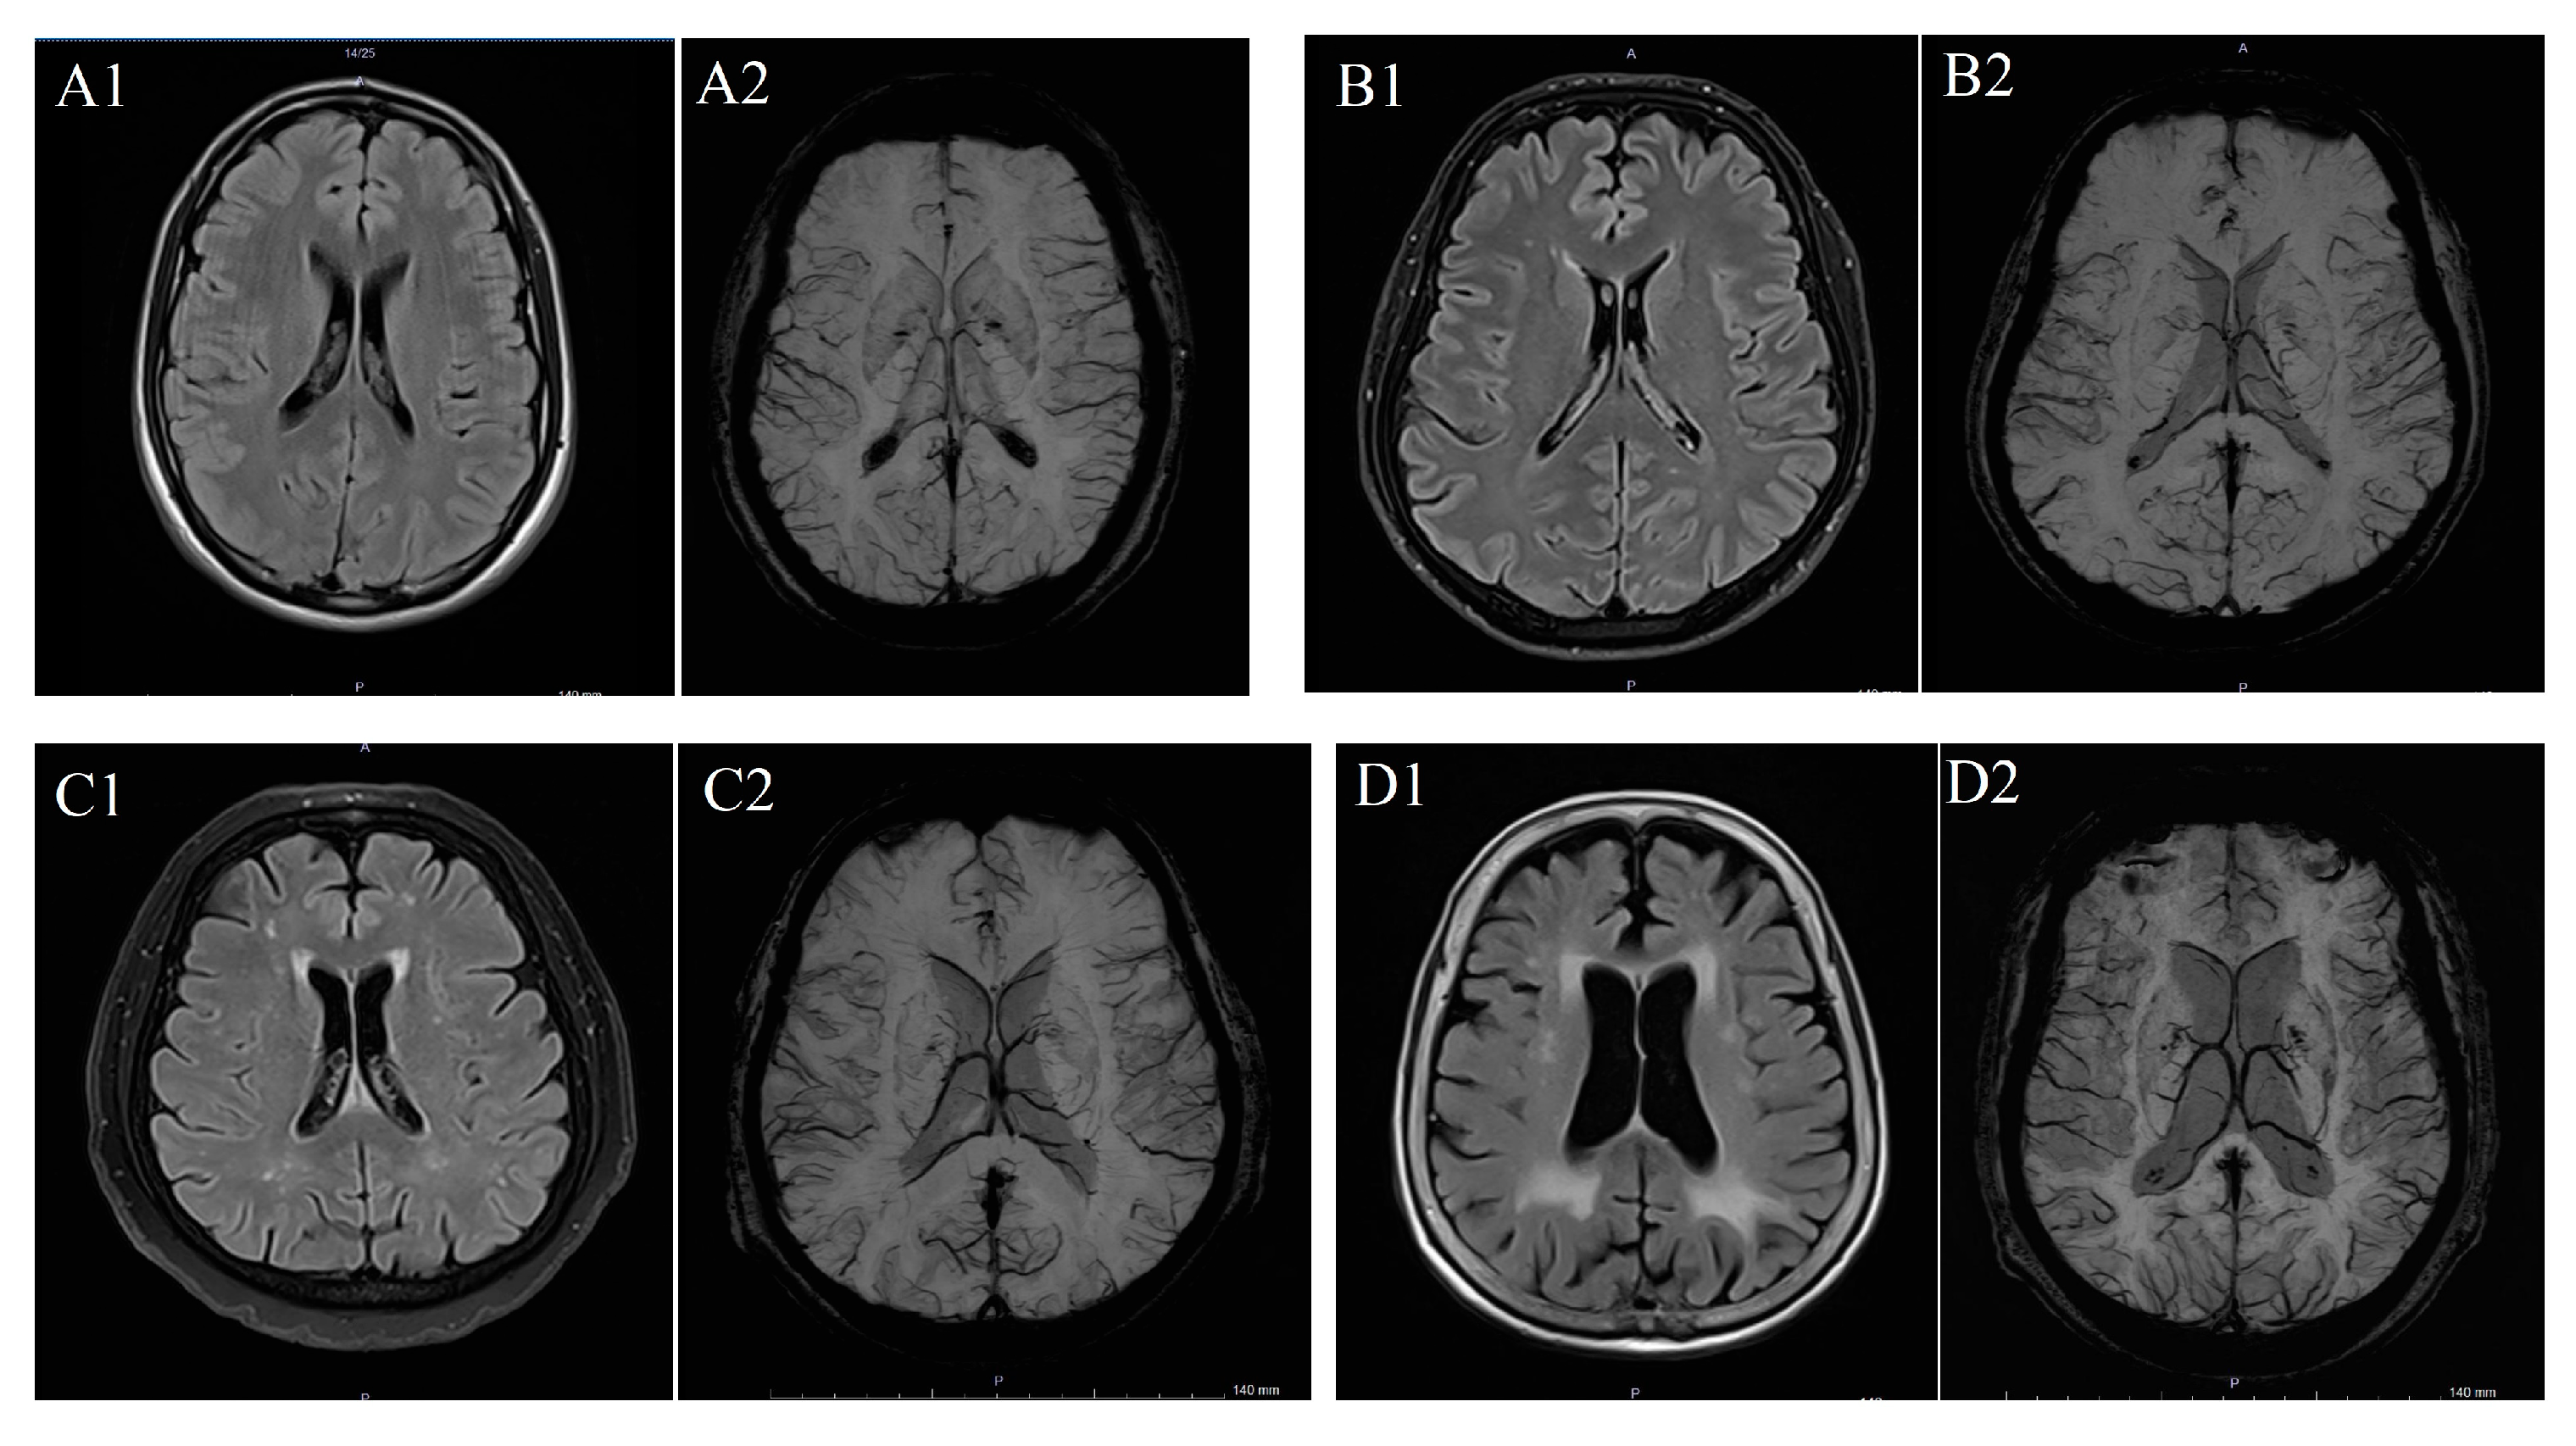

To determine WMH severity, the Fazekas scale was applied to FLAIR MRI data in the axial plane, following standard guidelines [11]. According to this scale, WMH was scored in categories between 0 and 3: “0” meaning absence of WMH; “1” meaning dotted WMH; “2” meaning early combined WMH; and “3” meaning WMH in large combined areas (Figure 1) [15]. The scale was selected due to its widespread clinical use, reproducibility, and suitability for retrospective MRI-based evaluation of WMHs.

Figure 1.

(A) T2 FLAIR (A1) and SW (A2) imaging in a patient with Fazekas 0 case, (B) T2 FLAIR (B1) and SW (B2) imaging in a patient with Fazekas 1 case, (C) T2 FLAIR (C1) and SW (C2) imaging iin a patient with Fazekas 2 case and (D) T2 FLAIR (D1) and SW (D2) imaging in a patient with Fazekas 3 case.